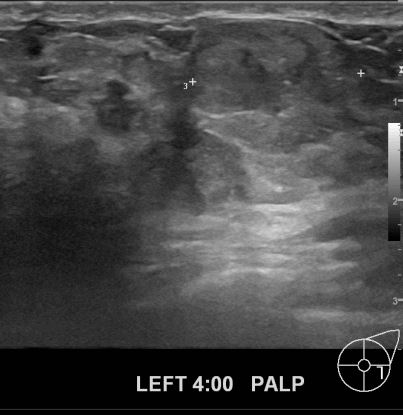

상기 환자 40대여성분으로 건강건진후 이상소견으로 내원하셔셔 좌측에 의심스러운

부분 조직검사 시행후 유방암으로 진단되었읍니다.